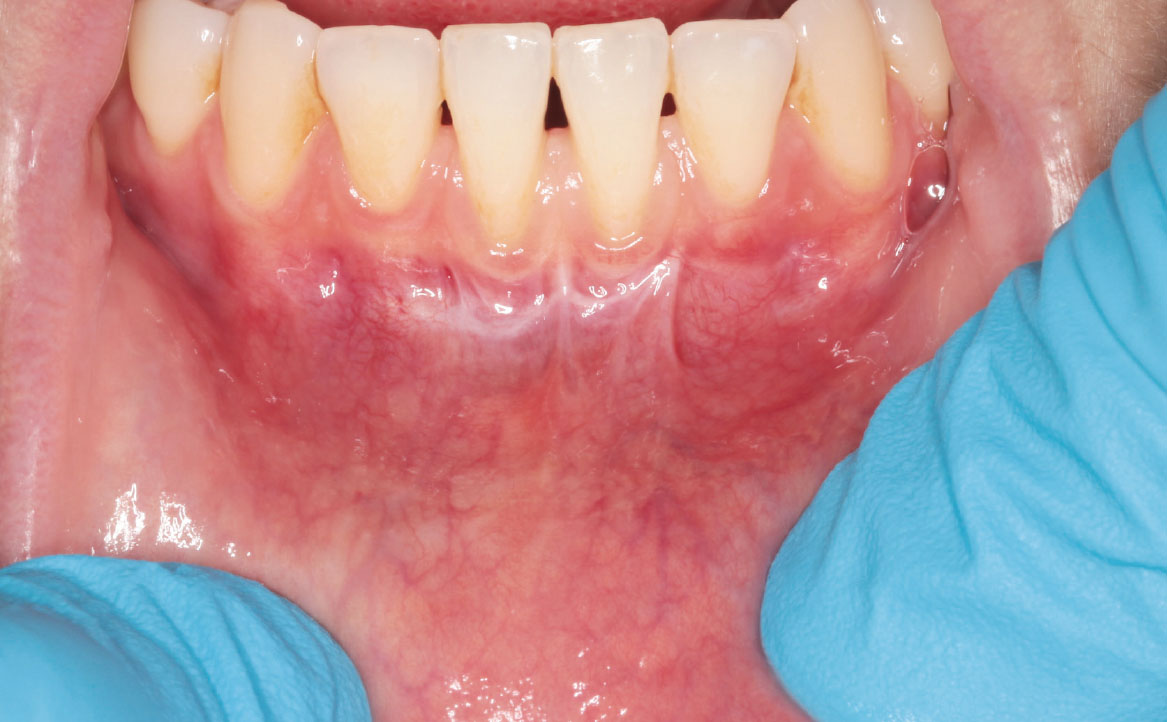

Il caso descritto riguarda una giovane paziente di 31 anni che si è presentata presso l’Unità Operativa di Odontostomatologia dell’Ospedale di Parma per recessioni gengivali di grado I di Miller della superficie vestibolare degli elementi 3.1 e 4.1. La paziente ha riferito deficit di coagulazione congenito e allergia alla mepivacaina.

All’esame obiettivo si è riscontrata scarsità della profondità del vastibolo in zona mandibolare anteriore. Si è deciso perciò di intervenire chirurgicamente eseguendo una vestibuloplastica inferiore con laser Nd:YAG.